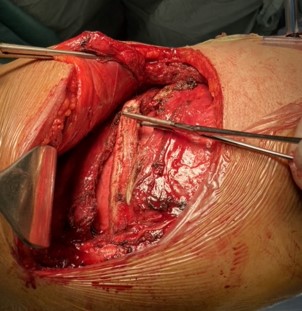

Chest wall stabilization

Rib fractures are by far the most common consequence of chest trauma, even when minor. The presence of multiple rib fractures, sometimes fragmented and/or displaced, sometimes with fragments protruding into the pleural cavity, or the presence of flail chest, cause intense chest pain and significantly affect the respiratory dynamics of the patient. In particular, they can cause severe respiratory failure, often requiring intubation and prolonged hospitalisation in intensive care unit. In addition, impaired respiratory dynamics lead to shallow breathing and of bronchial secretions retention, with a very high risk of pneumonia development.

In recent years, chest wall stabilisation surgery has developed, especially in the United States. The advantages of this surgery are: a) significant reduction in chest pain, b) improvement in respiratory dynamics, c) the possibility of extubating the patient more quickly, allowing for earlier discharge from intensive care, and d) much faster functional recovery, with a quicker return to daily life and work.